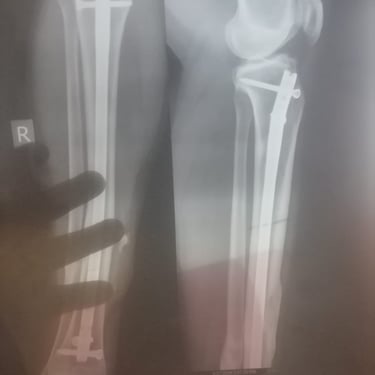

Imran Muwembe, founder of Rakai Vulnerable Home Center in Uganda, needs emergency surgery.

Years ago, while working in South Africa, he was hit by a car. His leg was saved with steel plates. After receiving a modest victim’s settlement, he returned to Uganda and used the money to start a home for orphaned children instead of rebuilding his own life.

Doctors advised that the plates be removed after four years, but he could not afford the procedure.

Now he is in extreme pain — with severe leg swelling, sacral nerve complications, and constant fever. Specialists warn the damage could become permanent without urgent treatment.

He needs $900 to cover surgery and essential hospital costs.